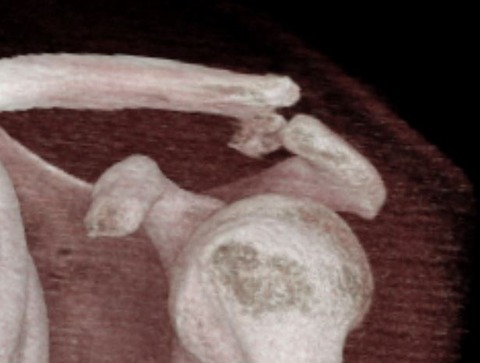

単純X線像では鎖骨遠位端骨折のようです。遠位骨片が小さいので、念のために3D-CTを撮像してみました。すると、どうやら肩鎖関節の関節内骨折のようです。

しかし、私はいまだかつて肩鎖関節脱臼骨折をみたことがありません。そのような骨折型が存在しても不思議ではないのですが、不思議と診たことはなかったです。

半信半疑で手術を施行しましたが、やはり肩鎖関節の鎖骨側が上方に脱臼していました。術野から鎖骨の肩鎖関節関節面がニョキっと出てきたときには、さすがに少し驚きました。

骨癒合さえすれば予後は良いのでしょうが、遠位骨片が小さくて母指の爪甲ぐらいしかありません。遠位骨片の幅も薄いので骨癒合するか否かが少し心配です。